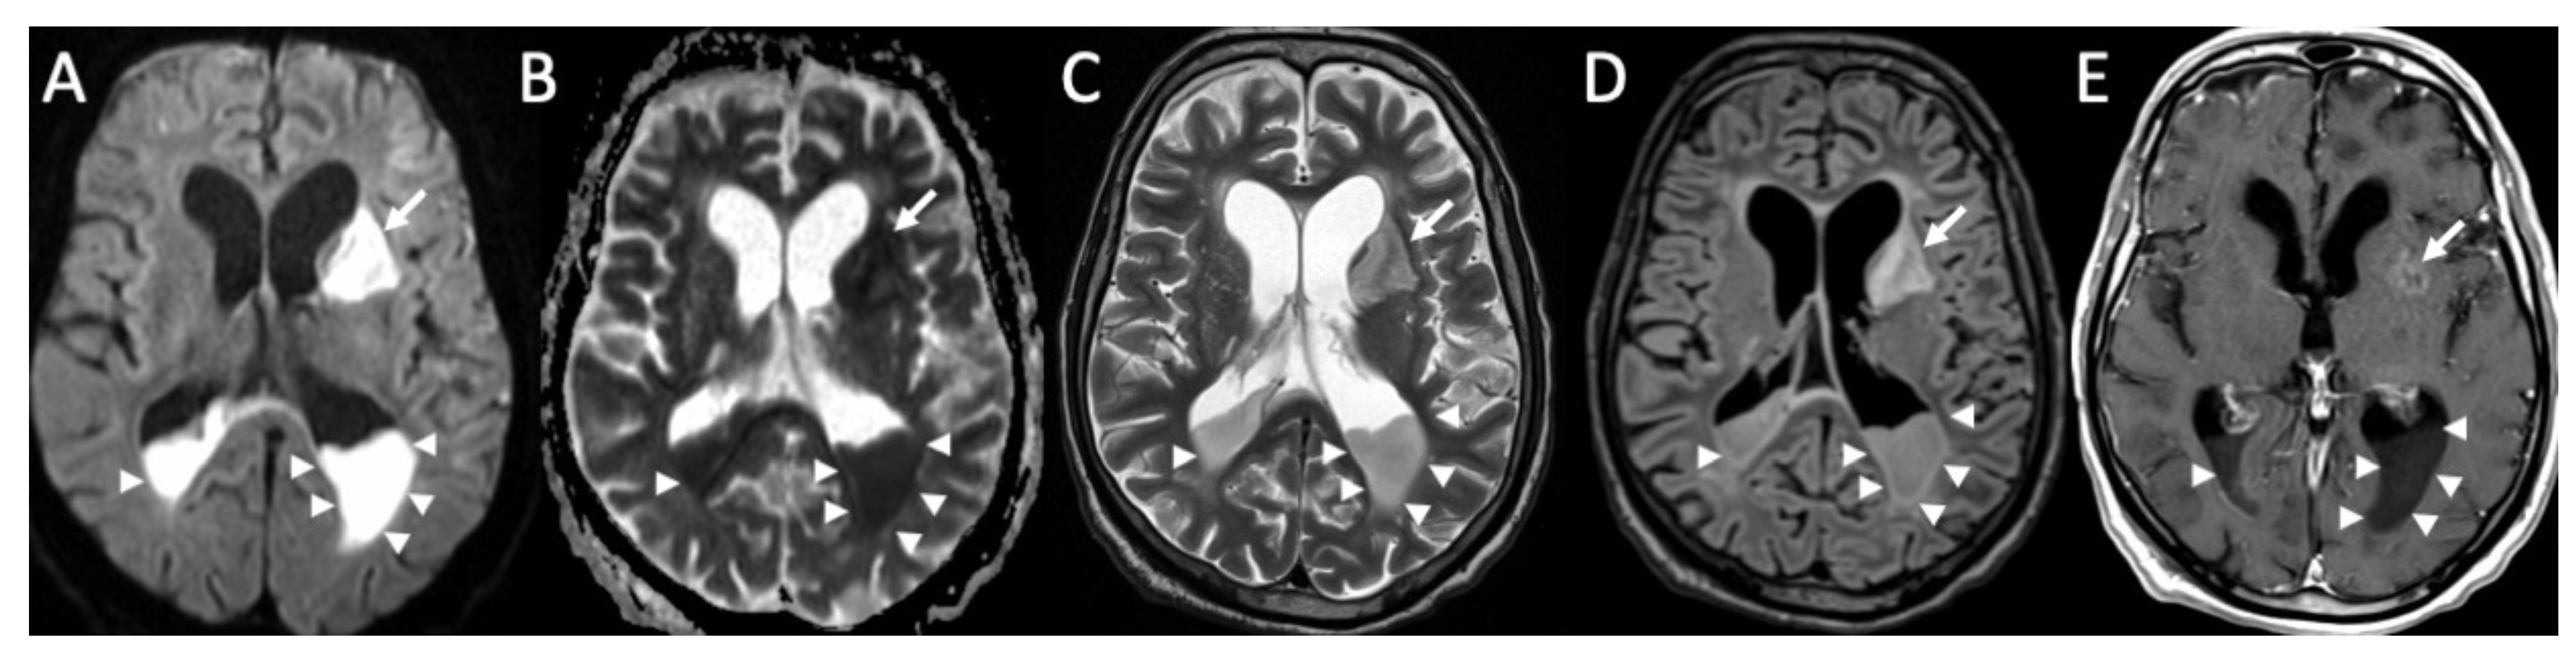

Figure 5.

Axial DWI (A), ADC (B), T2 (C), FLAIR (D), and enhanced T1 (E) show purulent material in the lateral ventricles bilaterally (arrowheads in A–E), with restricted diffusion, in a patient with Streptococcus Pneumoniae meningitis. Note also the recent ischemic lesions in the left nucleo-capsular region, which show faint contrast enhancement after contrast injection (arrows in A–E). There is also enlargement of the lateral ventricles due to hydrocephalus.